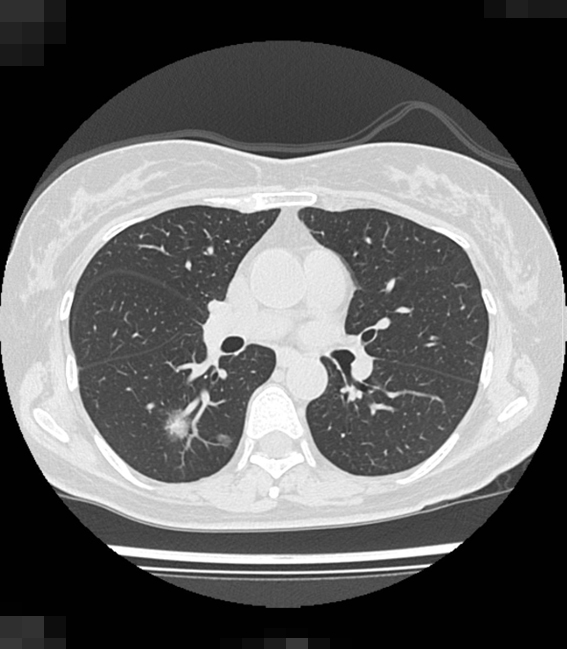

肺がんは年間7万5585人が死亡し、特に「肺腺がん」はタバコを吸わない人にも多いです。早期発見が難しく、CT検査が推奨されます。アジア人では遺伝子の個人差がリスクに影響します。

40歳を過ぎたら一度はCTを撮ってみてはいかがでしょうか。

女性肺がんの急増、女性と喫煙、女性肺がんと遺伝子・性ホルモン、女性肺がんとゲフィチニブ、女性肺がんと化学療法・緩和ケアそして女性肺がんとCT検診などについて解説します。